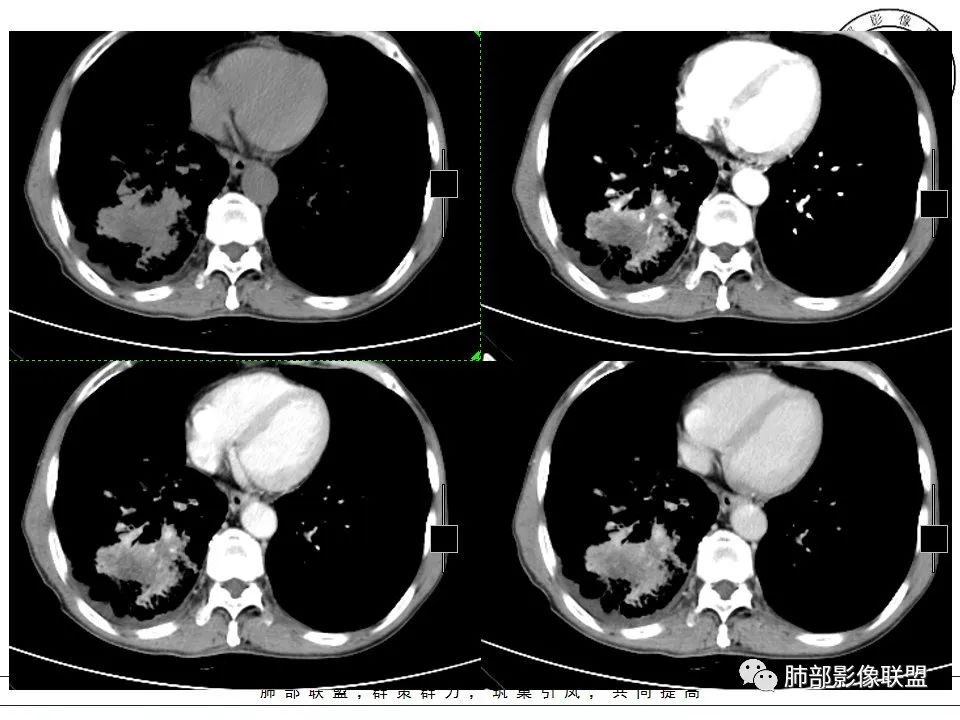

右下肺外后基底段不规则实变,其周散在GG0,边界清楚,病灶由外朝内蔓延,包埋相应支气管,整体体积未见减小,坏死区不彻底较模糊,其间可见穿行血管受侵僵直、弯曲,纵隔及右肺门淋巴结肿大融合坏死,老年男性,慢性病程,反复咳嗽,抗炎效果不佳,考虑恶性肿瘤,以低分化腺癌可能。| 医学百科网 | YxBaike.Com

右肺下叶不规则肿块,周围大片状磨玻璃,支气管远端堵塞,见条形粘液栓低密度影,增强扫描不均匀强化,血管造影征,粘液栓延迟强化,右肺门、纵隔淋巴结肿大融合,环形强化,边界清,右中间段、中下叶支气管狭窄,右下肺静脉细小;老年男性,慢性病程,肺气肿背景,吸烟史,抗感染治疗效果不佳,考虑恶性,小细胞肺癌?低分化腺癌?肺内病灶与右肺门、纵隔淋巴结强化不符合,还需与结核鉴别,不排外2元论! 医学百科网 | YxBaike.Com

患者老年男性,反复咳嗽半年余。抗感染治疗效果欠佳。胸部CT:右肺下叶大片实变占位影,沿支气管走行,形态不规则,密度不均,其内可见低密度粘液栓,血管造影征,肺门侧支气管血管束增粗,支气管管腔狭窄,支气管进入病灶堵塞,胸膜牵拉,周围大片磨玻璃影,小叶间隔增厚,斜裂多发结节,胸膜不规则增厚,胸腔少量积液,纵膈多发淋巴结肿大并融合,且内见低密度区,环形强化,综合考虑恶性病变,腺癌可能性大。鉴别结核。 医学百科网 | YxBaike.Com

双肺胸膜下肺气肿,右肺肺门及中下叶肿块,形态不规则中叶病灶包绕支气管生长,支气管略狭窄,下叶支气管似有堵塞,病变内密度不均匀,平扫可见低密度坏死,增强后可见环形不均匀强化,有血管穿行,病灶边缘彭隆,分叶、毛刺,牵拉胸膜,胸膜下有少量胸水,胸膜不光滑,有结节感,纵隔淋巴结肿大并环形不均匀强化,中年男性,有大量吸烟史,考虑恶性:小细胞癌,鳞癌,鉴别放线菌

非常纠结,老年男性,吸烟史,右肺下叶病变,有肿块,深分叶,内部坏死,粘液,支气管扩张,看着像炎性可能,结核?放线菌?但是病变周围小叶间隔增厚,蜂窝,纵隔及肺门多发淋巴结肿大伴环形强化,恶性考虑,低分化腺癌,癌肉瘤,综合考虑恶性,炎性鉴别 医学百科网 | YxBaike.Com

右肺下叶后基底段不规则软组织肿块,呈轻度膨胀改变,边缘可见蠕虫样凸起,肿块沿支气管向肺门侵犯,致右肺下叶支气管开口变窄,周围见软组织肿块,纵隔多组淋巴结肿大,增强扫描肿块不均匀强化呈“沼泽样”改变,其内穿行血管变细,肺门及纵隔呈“冰冻样”改变,综上所述符合小细胞肺癌影像学表现。 医学百科网 | YxBaike.Com

老年男性,以咳嗽半年为主诉,曾给予抗感染治疗效果欠佳。胸部影像示纵隔及右肺门淋巴结肿大,右肺下叶占位性病变,并周围大片状磨玻璃影。增强扫描纵隔淋巴结呈环形强化,内部坏死明显边界清楚,淋巴结粘连融合。右肺下叶肿块增强扫描内部坏死明显,支气管远端截断,延迟强化。考虑慢性感染性疾病,如放线菌,奴卡菌。与腺癌并转移鉴别。

右肺下叶大片实变影,沿支气管走行,形态不规则,密度不均,其内可见低密度粘液栓,血管造影征,肺门侧支气管血管束增粗,支气管管腔狭窄,支气管进入病灶阻塞,胸膜牵拉,周围大片磨玻璃影,小叶间隔增厚,斜裂多发结节,胸膜不规则增厚,胸腔少量积液,纵膈多发淋巴结肿大并融合,环形强化,肺气肿背景,胸膜下多发肺大泡,考虑肺炎型肺癌。鉴别结核。 医学百科网 | YxBaike.Com

老年男性,吸烟,肺气肿背景。右肺门及下叶不规则肿物,内部沼泽样强化,血管包埋挤压,纵隔淋巴结肿大融合,周围脂肪间隙显示。考虑小细胞肺癌。 医学百科网 | YxBaike.Com

老年男性,反复咳嗽半年,体重下降20公斤。吸烟指数2000(50×40), 影像表现:肺气肿背景,右肺下叶斑片状实变影,内部支气管部分扭曲稍扩张,周围广泛小叶间隔增厚伴结节状改变,中间部分小叶间内间隔增厚,呈细网格征,远端阻塞形成空气潴瘤征,增强后呈斑片状不规则坏死,少部分血管破坏,多数血管走行较好。纵隔内淋巴结广泛肿大,坏死,呈环状稍强化,部分呈薄环状改变,部分环较厚。1、综合分析:疾病谱,肺炎型肺癌,肺结核,淋巴瘤,结节病。2、初步考虑肺炎型肺癌可能(鳞癌>腺癌),鳞癌支持点:老年男性,长期吸烟史,肺气肿背景,远端阻塞性空气潴留,实变区中间坏死,支气管扩张扭曲,纵隔淋巴结坏死。鳞癌不支持点:实片区坏死不够彻底,非典型湖泊样坏死,中间多数血管走行较自然。鳞癌淋巴结转移相对更少见一些。腺癌支持点:实变区坏死情况及淋巴结表现以及癌淋形成支持。腺癌不支持点:老年男性,长期吸烟史,肺气肿背影,远端阻塞性空气潴留。鉴别诊断:1、肺结核,反复咳嗽半年,体重减轻20斤支持,淋巴结环形强化,尤其是部分呈薄环形强化支持,但无结核中毒症状,坏死不彻底不支持,纵隔淋巴结部分壁不均匀,不支持。所以结核可能性较小。2、淋巴瘤,纵隔淋巴结广泛增大及实变区部分血管走行较自然支持。实变区坏死及部分血管有部分不支持,淋巴结坏死不支持。所以可能性也不大。

患者老年男性,慢性病程,干咳,无痰,既往有大量吸烟史。胸CT:右肺下叶支气管明显狭窄,右肺下叶外后基底段占位性病变,病灶周围可见毛玻璃样渗出影及肺气肿。增强纵膈窗可见:右肺下叶实性占位病灶内可见低密度区,并可见血管造影正,2R 4R 4L 7及右肺门淋巴结明显肿大,部分肿大淋巴结可见融合坏死。

综合考虑患者为恶性病变———腺癌? 医学百科网 | YxBaike.Com

老年男性,不良吸烟史慢性病程,干咳半年,抗感染无效,影像:双肺胸膜下旁间隔气肿,右肺下叶大块样实变,有占位效应,胸廓无缩小,彭隆分叶,胸膜增厚牵拉凹陷,周围磨玻璃影边界不清,小叶间隔增厚,斜裂受累有结节感,支气管截断,近端环形狭窄,纵膈窗提示不均匀延迟强化,坏死粘液栓,累及血管纤细,远端伴有蜂窝,双侧肺门、纵膈、多组淋巴结肿大,融合,中央坏死环形强化,上腔静脉受压,考虑恶性可能性大,腺癌? 医学百科网 | YxBaike.Com

老年男性,干咳半年。右肺门及纵隔淋巴结肿大,内部不均匀坏死,无坏死区可见强化,符合恶性转移性淋巴结,左肺门无明显淋巴结肿大,考虑跟右下肺病变相关。右下肺肿块,边缘膨隆,近端支气管见鼠尾状截断,内见支气管粘液栓,周围见斑片状影及牵拉性改变,周围间质增厚。综上,考虑右肺下叶恶性肿瘤(腺癌)并右肺门、纵隔淋巴结转移,粘液腺癌可能性大。

男,67岁,反复咳嗽半年。右下叶磨玻璃影背景见团块影,部分边缘膨隆,部分平直,似有分叶,近端支气管狭窄,增强有强化,内有条状低密度灶(粘液栓?),血管稍变小,走形尚正常。纵隔多发环形强化的肿大淋巴结。考虑:1.淋巴瘤,依据:病灶内似有血管漂浮,纵隔多发肿大淋巴结。2.肺癌,依据:肿块状病灶,部分边缘膨隆、分叶,近端支气管狭窄。3.肺结核,依据:结核是妖。 医学百科网 | YxBaike.Com

老年男性,有大量吸烟史,反复咳嗽半年。纵隔及肺门多发肿大淋巴结,多发融合并有坏死,坏死边界清,各级支气管外压性狭窄,右肺下叶大肿块,内有多灶性坏死,外周有磨玻璃影,伴蜂窝状改变,中度强化,局部胸膜肥厚有少量胸腔积液。考虑恶性肿瘤,腺癌可能性大,鉴别淋巴瘤,结核?

2.右肺下叶大范围磨玻璃密度片影,边界不清,小叶间隔增厚明显,胸膜下区域见气肿。 医学百科网 | YxBaike.Com

3.片影中央见较大块状影,边界可分辨,不规则分叶,未显示毛刺,可见棘突及胸膜牵拉。

块影密度不均匀,可见明显液化区。明显不均匀环形强化,病灶内血管未见明显异常。

块影明显支气管相关,中间段支气管有狭窄,后段支气管低密度阻塞(局部未强化),未见枯枝征。 医学百科网 | YxBaike.Com

4.后基底段多发小结节影。 医学百科网 | YxBaike.Com

5.右肺门及纵隔见多数明显肿大淋巴结,环形或分隔样强化,这点表现相当显著。